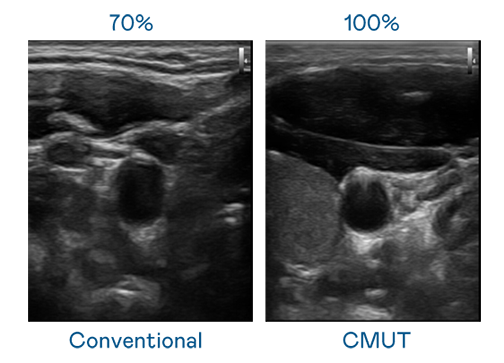

CMUT 技術是一種用電容式微機電元件來產生超音波訊號的技術。與傳統 PZT 壓電式技術相比,CMUT 頻寬增加 30%,更寬頻的超音波訊號讓影像解析度大幅提升,是實現高影像品質醫療超音波掃描、促進精準醫療發展的關鍵技術。

大頻寬帶來超清晰影像

超音波影像的解析度高低,首先取決於探頭能發出的訊號頻寬。金年会jinnianhui官方在线登录 CMUT 可提供高清晰的超音波訊號,提供高頻寬、高靈敏度、影像紋理細節更高的超音波影像,協助醫護人員縮短影像判讀時間及利用精準的醫療影像進行診斷。